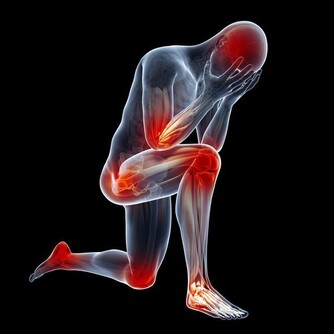

胰腺癌的常見症狀包括背痛、胃痛、體重異常減輕等,最為明顯的跡像是皮膚和眼白開始泛黃。另外,一個不容忽視的事實是,有超過30%的胰腺癌患者在確診患上這種惡性腫瘤前,被診斷出2型糖尿病。醫生認為,這可能是胰腺腫瘤干擾了胰島素分泌的結果,才會導致出現糖尿病。